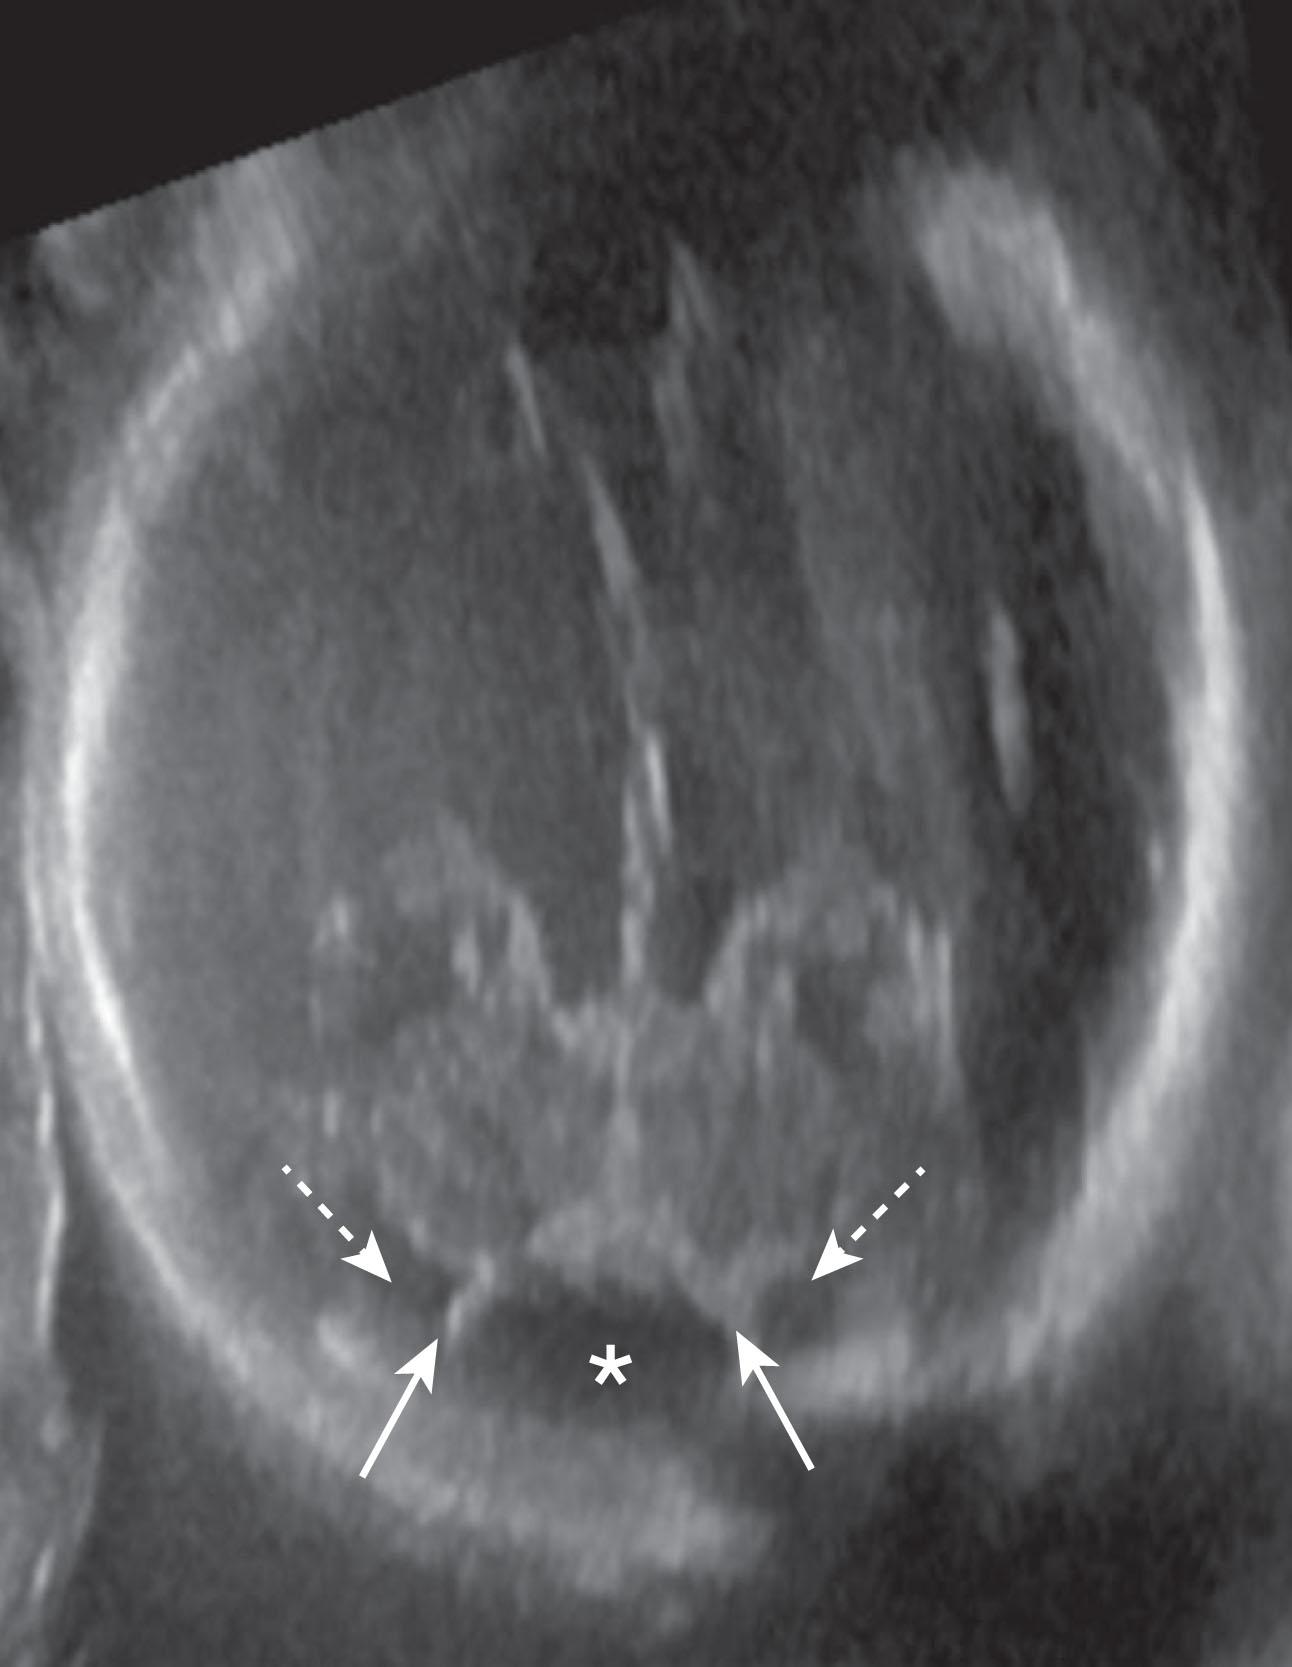

Fig. 4.17, Blake pouch cyst. Fetal magnetic resonance imaging (T2-weighted) at 37 weeks’ gestation. (A) Midline sagittal view showing enlarged fourth ventricle and widened tegmento-vermian angle (dotted lines) . Notable normal features include the size and lobulation of the vermis, torcular Herophili location, cerebellar hemispheres and brainstem, and fastigial point (arrow) . (B) Axial view showing enlarged fourth ventricle (asterisk) with cystic lesion (arrow) in continuity.

Fig. 4.18, Blake pouch cyst. Fetal ultrasound axial view in a 23-week-old fetus showing the septa (solid arrows) of the Blake pouch (asterisk) with the subarachnoid space on both sides (dashed lines) . The Blake pouch cerebrospinal fluid space is usually more echolucent than the adjacent subarachnoid space, which is bridged by pial-arachnoid septations.